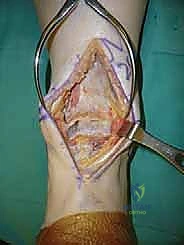

يقوم الدكتور هطيف بعمل شق طولي دقيق في الجزء الأمامي من الكاحل، طوله حوالي 10-15 سم. يتم تشريح الأنسجة بعناية فائقة للوصول إلى المفصل.

* الحماية العصبية الوعائية: هذه هي الخطوة الأكثر حرجاً. يتم تحديد الحزمة الوعائية العصبية (الشريان الظنبوبي الأمامي والعصب الشظوي العميق) وسحبها برفق شديد لحمايتها من أي ضرر جراحي.

3. إزالة النتوءات العظمية وتحضير المفصل (Debridement)

بمجرد كشف المفصل، يقوم الجراح بإزالة الغشاء الزلالي الملتهب والزوائد العظمية (Osteophytes) التي تعيق الحركة. هذه الخطوة ضرورية لاستعادة المعالم التشريحية الطبيعية قبل إجراء القطع العظمي.